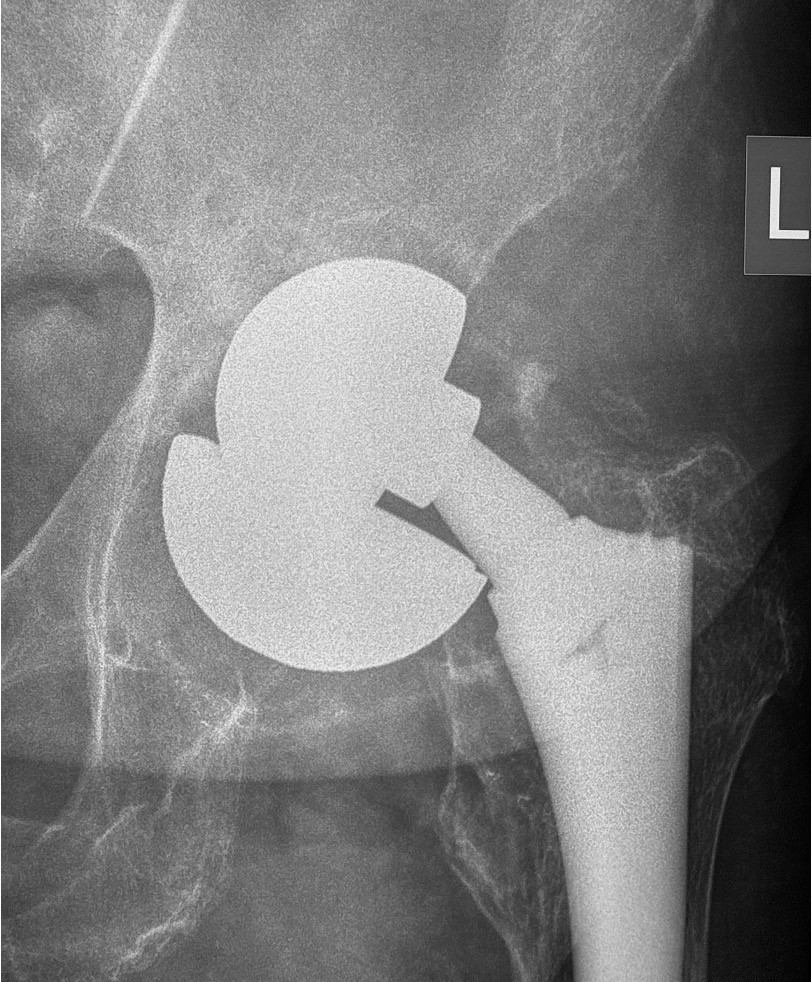

Οι συχνότερες αιτίες αποτυχίας μιας αρθροπλαστικής είναι η η χαλάρωση των μοσχευμάτων, η αστάθεια και το εξάρθρημα της αρθροπλαστικής, τα περιπροθετικά κατάγματα και η πιο δύσκολη επιπλοκή της μολυσμένης αθροπλαστικής.

Κάθε περίπτωση έχει ιδιαιτερότητες που σχετίζονται με το είδος της αρθροπλαστικής που πρέπει να αναθεωρηθεί, με τον τρόπο που θα αφαιρεθούν οι παλιές προθέσεις, με την τεχνική κάλυψης των οστικών ελλειμάτων που συνήθως υπάρχουν στην περιοχή, με τον τρόπο που πρέπει να στερεωθούν τα καινούργια υλικά, με τον χειρισμό των μαλακών μορίων κ.α.

Στις περισσότερες περιπτώσεις η επέμβαση αναθεώρησης των αρθροπλαστικών δεν έχει καμία σχέση με τις τεχνικές και τα υλικά που χρησιμοποιούνται στις αρχικές αρθροπλαστικές.